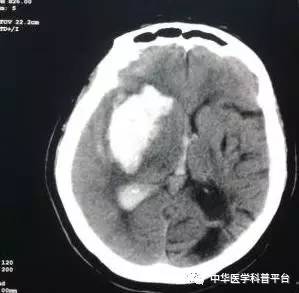

这次收的是一个40出头的男人,上班的时候被人发现倒在地上,送到医院后发现已经昏迷不醒。双侧瞳孔散大固定,头CT图如下

相关科室会诊后均建议保守治疗,旁边的妻子泣不成声,家住湖北的她听到丈夫的噩耗后,连夜从老家赶到医院,看到的却是再也没醒过来的丈夫,家中还有一个刚刚满1岁的孩子和年迈的老母亲。

上级医生的查房考虑这是一种血管畸形引起的脑血管破裂出血进而形成脑疝。